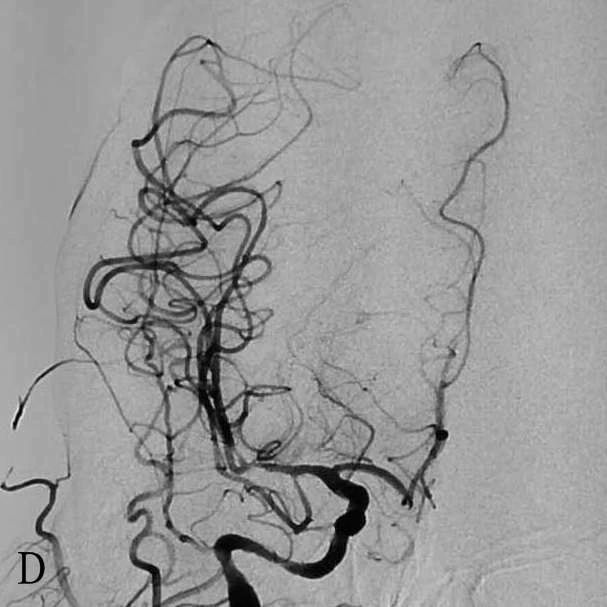

女性,45岁,房颤史,因风湿性心脏病、心功能不全在本院心内科住院期间突发昏迷、抽搐、呕吐0.5h进入卒中绿色通道。查体:中度昏迷,刺痛四肢无活动,NIHSS28分。多模CT提示双侧颈内动脉闭塞, RAPID显示双侧大脑半球低灌注。急诊行球囊导引导管辅助支架取栓,成功开通双侧颈内动脉,ORT时间4h,术后出现严重脑梗塞、脑水肿,双侧大骨瓣减压后仍死亡。

D:取栓后右侧ICA造影正位显示右侧ICA mTICI3级再通

E:取栓后左侧ICA造影正位显示左侧ICAmTICI3级再通